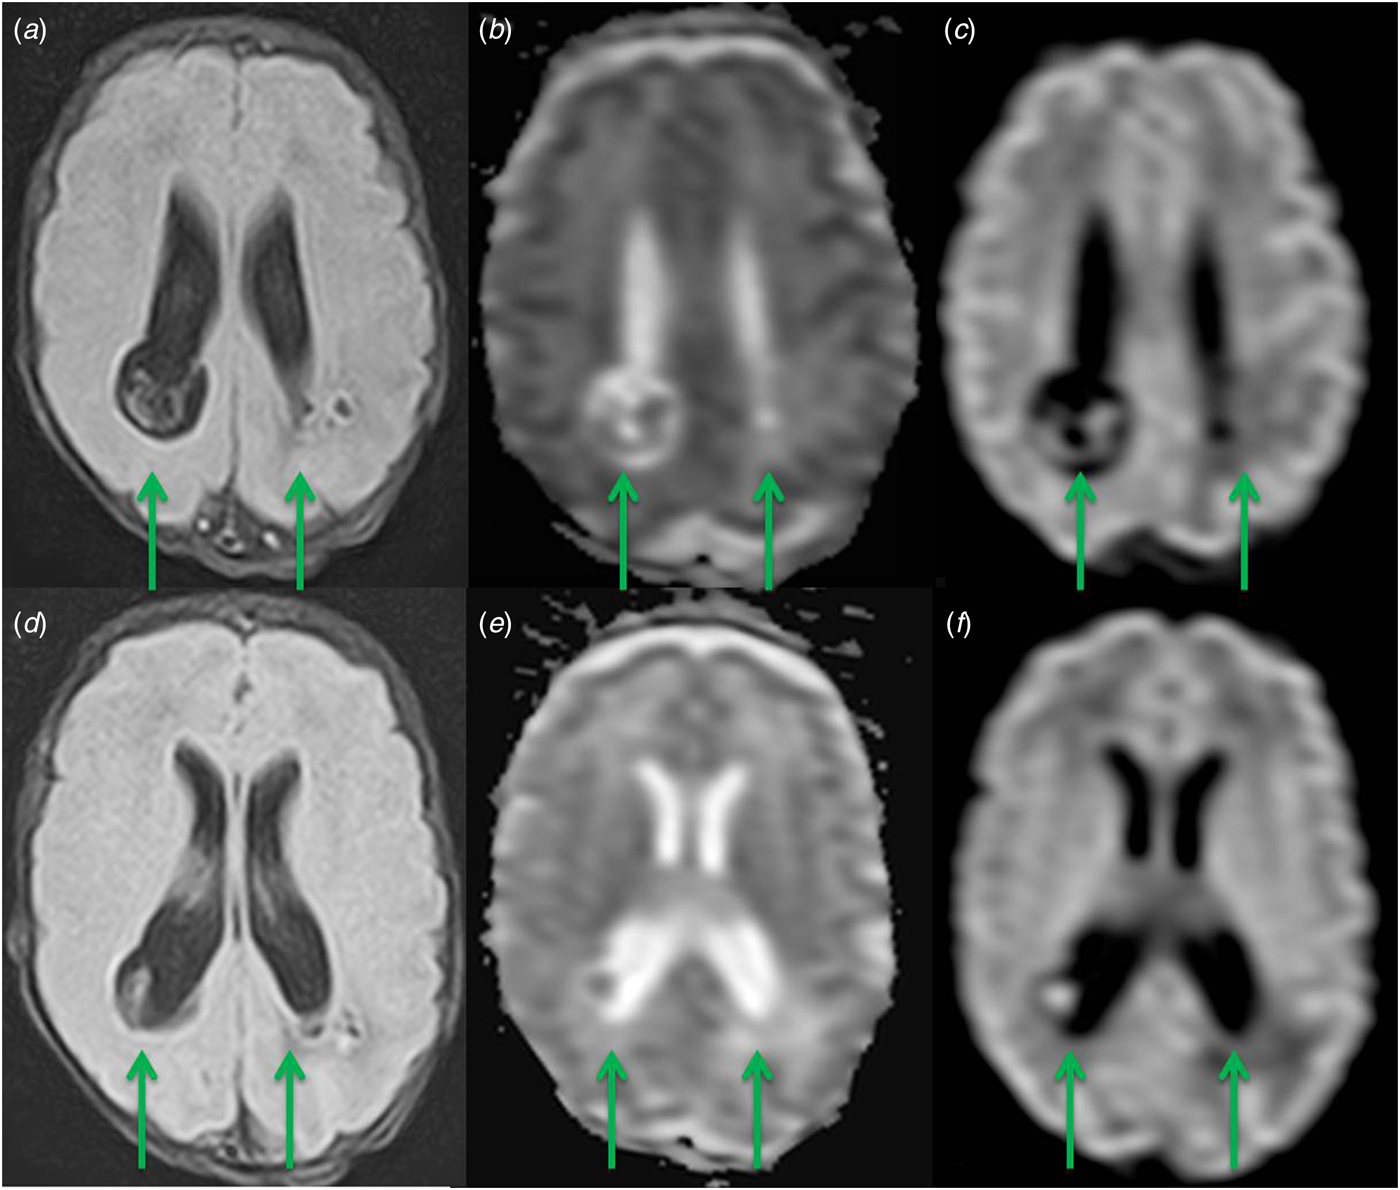

Fig. 2. Presence of multiple focal lesions in the parietal lobes, with a hyperintense centre and a mildly hypointense rim on FLAIR images (a, d). The central core of the masses restricts strongly on DWI (b, e) and ADC (c, f). MRI features are consistent with cerebral abscesses.